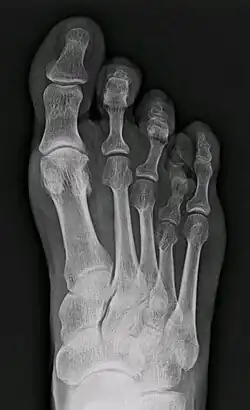

Брахиметатарзи́я (англ. brachymetatarsia, др.-греч. βραχυμεταταρσια: βραχυ — короткий; μεταταρσιο — плюсна) — это возникающая вследствие неизвестных причин редкая аномалия развития (укорочение) одной или нескольких плюсневых костей. Преждевременное закрытие зоны эпифизарного роста приводит к появлению дефекта: палец стопы (чаще всего четвёртый, но может быть и любой другой)[1], длина которого не изменена, располагается несколько проксимальнее и выше остальных. Брахиметатарзия может быть одно- или двусторонней, с преобладанием последней (72% случаев)[1]. Если затронуто более одного пальца на одной ноге, то такой порок называется брахиметаподией[2]. Укорочение первой плюсневой кости вызывает состояние, известное как палец Мортона, которое, впрочем, рассматривается как вариант нормы, поскольку не приводит к существенным изменениям внешнего вида стопы и появлению жалоб.